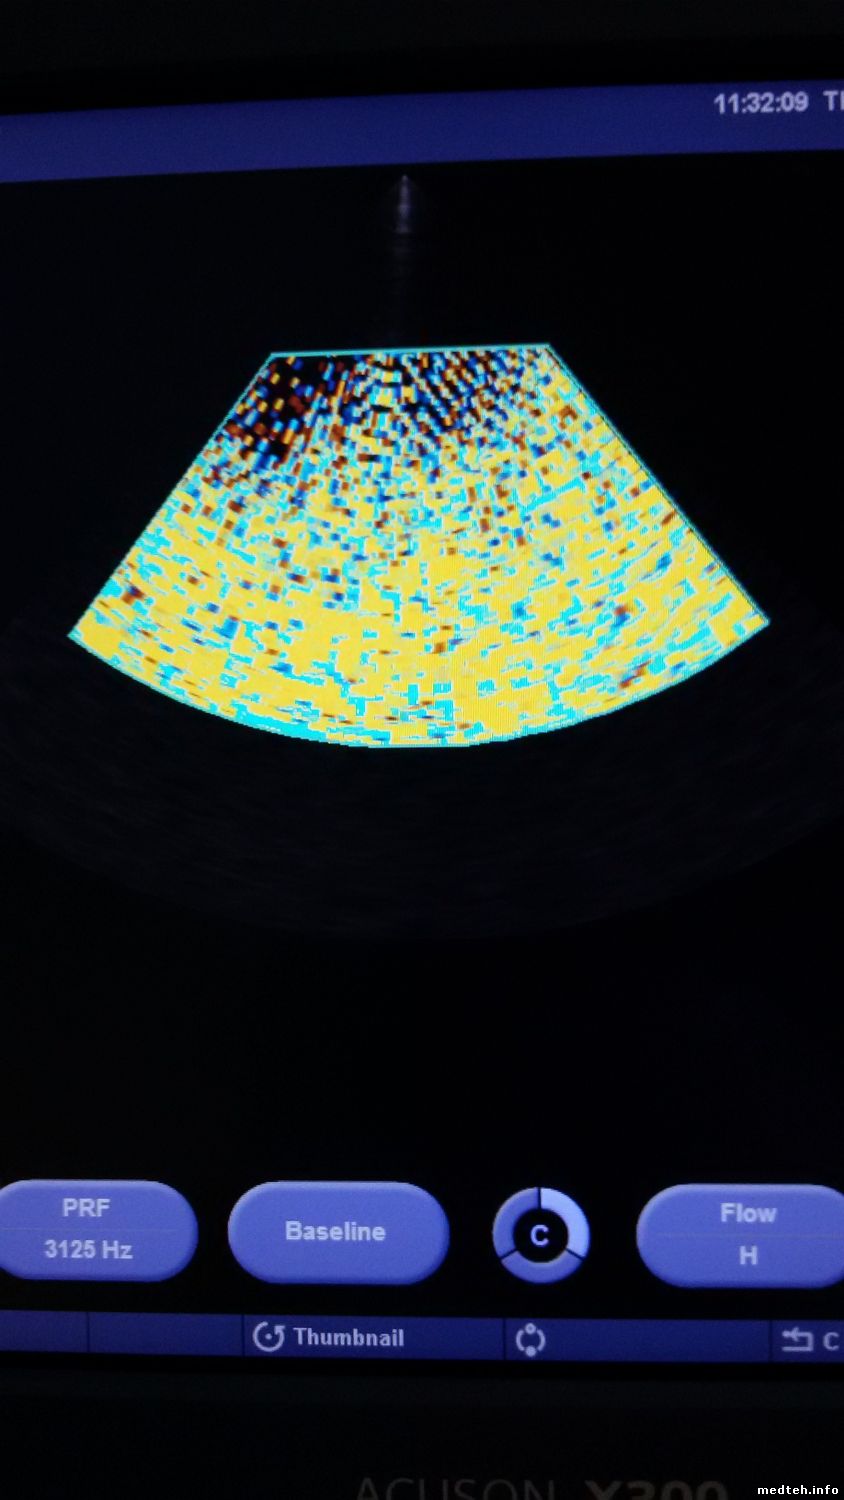

День добрый. Понимаю, что тема несколько устарела, но столкнулся с подобной проблемой как Senergy. Аппарат, siemens acuson x300, с периодически проявляющейся проблемой, фото прилагаю. Заземление проверенно, для пробы включал от ИБП с синусом на выходе, проблема все равно проявляется. В логах все чисто, нет ни одного FAIL, залез в блок питания что слева и осцилом проверил все напряжения в момент когда есть и нет этой проблемы, все напряжения в норме. Как говорит клиент, проблема проявляется и при смене датчика, но я лично этого не видел, так что остается "верить" словам клиента. Уже и не знаю, что еще можно проверить. Может кто чего подскажет

4305190.jpg (102.2 Kb) · 4516914.jpg (115.8 Kb)